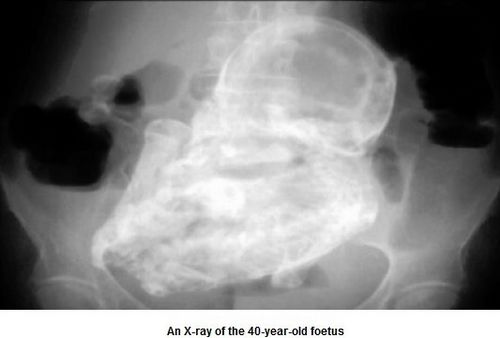

中新网12月13日电 据外媒报道,哥伦比亚首都波哥大一名82岁老妇,8日因腹痛就医,医师惊讶地发现,造成她腹痛的原因,竟是一个已形成40年的“石胎”。

起初医师以为老妇是因为寄生虫或是胆结石导致腹痛,但察觉老妇腹部有异状,经X光检验才查出老妇体内居然有一个胎儿,而且胎儿在老妇体内长达40年,由于胚胎未在子宫里发育,移到患者的腹腔,导致胚胎无法正常生长,钙化后形成“石胎”。

德州内分泌与生殖专家伯格博士表示,子宫外孕(异位妊娠)通常的位置常在输卵管,少数案例发生在肠、卵巢,甚至在主动脉,这些罕见的位置对病患而言非常危险。这名老妇目前已转院,将接受手术移除“石胎”。